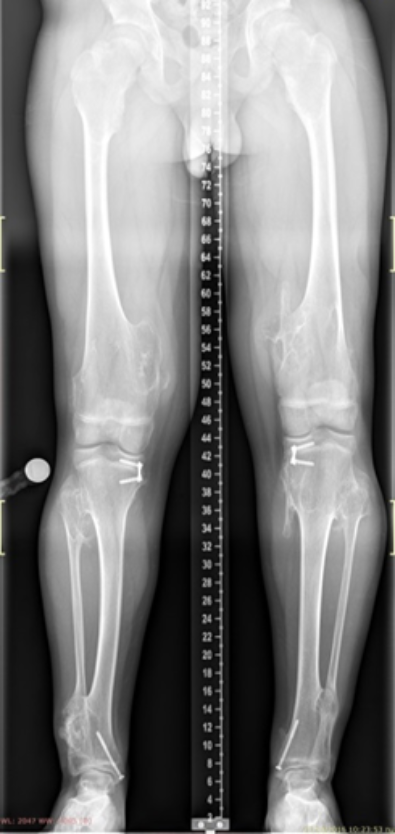

The images show a case of multiple osteochondroma which was operated by

Dr. Zenios in order to restore the mechanical axis.

Pre-operative

Post-operative